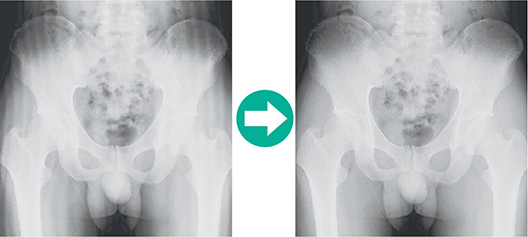

Obwohl es sich um ein kompaktes System handelt, gibt es keine Einschränkung hinsichtlich Handhabung und Bildqualität. Image Intelligence™, Fujifilms Bildverarbeitungstechnologie, verbessert den Bildkontrast und die Bildschärfe. FCR PRIMA T unterstützt die Diagnose durch eine gleichbleibende und optimierte Bildqualität.

Verbessert FCR-Bilder. Alle Bildbereiche werden verbessert